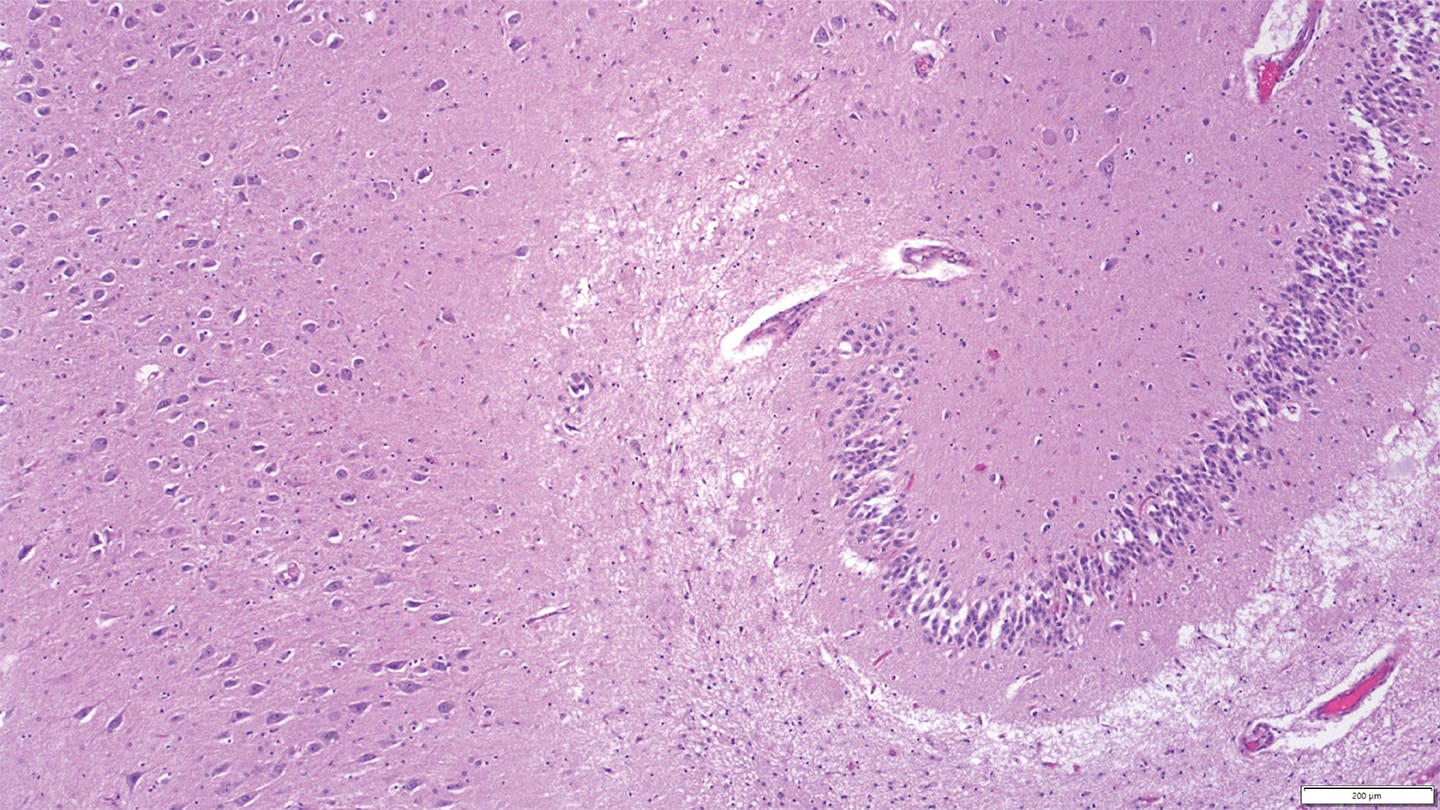

Feline dementia shares key pathological features with human neurodegenerative disease, study finds